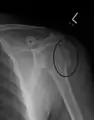

Proximal

Proximal humerus fractures most often occur among elderly people with osteoporosis who fall on an outstretched arm.[9] Less frequently, proximal fractures occur from motor vehicle accidents, gunshots, and violent muscle contractions from an electric shock or seizure.[10][5] Other risk factors for proximal fractures include having a low bone mineral density, having impaired vision and balance, and tobacco smoking.[11] A stress fracture of the proximal and shaft regions can occur after an excessive amount of throwing, such as pitching in baseball.[6]

Definitive diagnosis of humerus fractures is typically made through radiographic imaging. For proximal fractures, X-rays can be taken from a scapular anteroposterior (AP) view, which takes an image of the front of the shoulder region from an angle, a scapular Y view, which takes an image of the back of the shoulder region from an angle, and an axillar lateral view, which has the patient lie on his or her back, lift the bottom half of the arm up to the side, and have an image taken of the axilla region underneath the shoulder.[9] Fractures of the humerus shaft are usually correctly identified with radiographic images taken from the AP and lateral viewpoints.[12] Damage to the radial nerve from a shaft fracture can be identified by an inability to bend the hand backwards or by decreased sensation in the back of the hand.[5] Images of the distal region are often of poor quality due to the patient being unable to extend the elbow because of pain. If a severe distal fracture is suspected, then a computed tomography (CT) scan can provide greater detail of the fracture. Nondisplaced distal fractures may not be directly visible; they may only be visible due to fat being displaced because of internal bleeding in the elbow.[7]